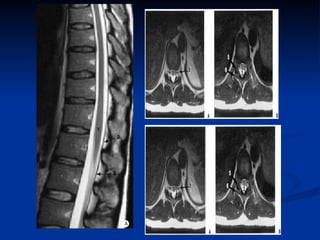

IRM dorsale  coupes  : une acquisition de repérage est réalisée dans un plan frontal  plans de coupe:  plan sagittal objectivant l'ensemble du rachis plan axial transverse pour une étude segmentaire épaisseur de coupe ne doit pas dépasser 3 à 4 mm dans le plan sagittal et 5 à 10 mm dans le plan axial

IRM dorsale Un examen IRM du rachis thoracique comprend le plus souvent : une séquence pondérée en T1, avec des coupes fines (3 à 4 mm) dans un plan sagittal  une séquence pondérée en T2 dans le plan sagittal ;  si besoin, des coupes axiales pondérées T1 ou T2 suivant l'indication.

Artéfacts  artefacts de flux :  espace sous arachnoïdien rétromédullaire thoracique, axiales T2 SE rapide    ne doit pas être confondu avec des dilatations vasculaires  artefacts de mouvement:  pulsations cardiaques et aux mouvements respiratoires L’ artefact de Gibbs  (artefact de troncature) hypo-intensité T1 et hyperintensité T2 linéaire centromédullaire parallèle à l’axe de la moelle    ne doit pas être confondu avec une fente syringomyélique. L’ artefact  de déplacement chimique peut effacer le signal de l’un des deux plateaux vertébraux sur les coupes sagittales et frontales pondérées en T1

IRM dorsale Unexamen IRM du rachis thoracique comprend le plus souvent : une séquence pondérée en T1, avec des coupes fines (3 à 4 mm) dans un plan sagittal une séquence pondérée en T2 dans le plan sagittal ; si besoin, des coupes axiales pondérées T1 ou T2 suivant l'indication.

Artéfacts artefactsde flux : espace sous arachnoïdien rétromédullaire thoracique, axiales T2 SE rapide  ne doit pas être confondu avec des dilatations vasculaires artefacts de mouvement: pulsations cardiaques et aux mouvements respiratoires L’ artefact de Gibbs (artefact de troncature) hypo-intensité T1 et hyperintensité T2 linéaire centromédullaire parallèle à l’axe de la moelle  ne doit pas être confondu avec une fente syringomyélique. L’ artefact de déplacement chimique peut effacer le signal de l’un des deux plateaux vertébraux sur les coupes sagittales et frontales pondérées en T1